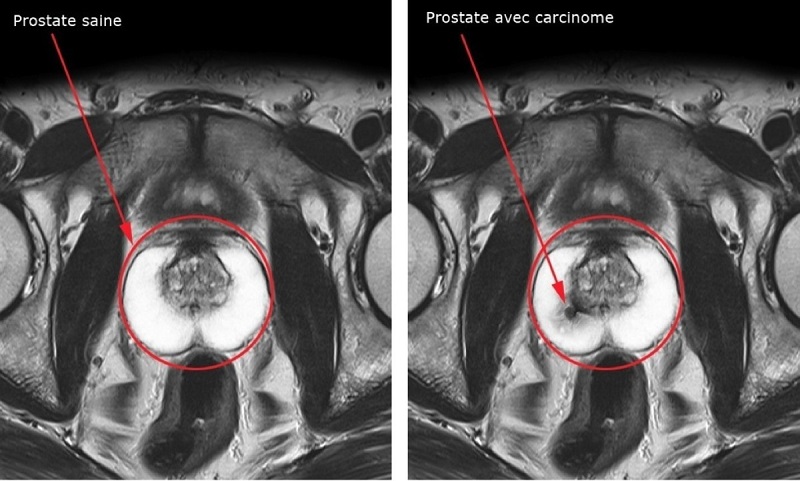

Maladie longtemps invisible, le cancer de la prostate est désormais détecté plus finement grâce à l’IRM. Des traitements ciblés, encore en test, pourraient révolutionner la vie des malades.

Trop d'ablations, trop de dosages sanguins, trop de biopsies… Après des années de sur-diagnostic et de sur-traitement du cancer de la prostate, la fin du tout-bistouri a commencé. Les progrès de l'imagerie médicale expliquent en partie cette petite révolution. "Grâce à l'IRM fonctionnelle, les radiologues savent désormais détecter le cancer de la prostate. Le produit au moment de l'examen se focalise sur des zones spécifiques. Cela traduit une anomalie de la vascularisation qui correspond souvent à une zone tumorale", décode le professeur Michaël Peyromaure, chef du service d'urologie à l'hôpital Cochin, à Paris. Contrairement à plusieurs autres cancers, repérables lors d'un scanner, celui de la prostate a longtemps été "un ennemi invisible" selon le professeur Abdel-Rahmène Azzouzi, chef du service d'urologie au CHU d'Angers : "L'IRM dans le cancer de la prostate, c'est un peu comme les lunettes infrarouges qui ont permis aux militaires de voir dans la nuit."

Cette avancée a mis en sourdine la controverse sur le test PSA (dosage dans le sang d'une protéine fabriquée par cette glande). Longtemps considéré comme un Graal de détection par les urologues quand les autorités pointaient son inutilité, le PSA est désormais un premier outil, limité, parmi d'autres. Grâce à l'IRM, les biopsies (prélèvements de tissu à l'aide d'une aiguille permettant de mesurer l'agressivité de la tumeur), vont devenir moins fréquentes. "On a comparé les biopsies faites dans des zones tumorales visibles en IRM et celles faites à l'aveugle dans toute la prostate", explique Michaël Peyromaure. Les tumeurs mises en évidence par l'IRM sont bien plus agressives. L'IRM s'impose donc comme un filtre entre le dosage PSA et les biopsies. Elle permet d'éviter les biopsies inutiles qui peuvent entraîner des complications, de mieux les cibler sur les zones suspectes et de sélectionner les tumeurs qui doivent être surveillées ou soignées."